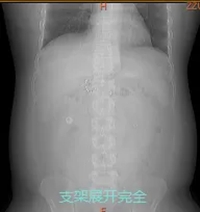

近日,消化内科二病区刘谦主任团队完成了医院首例胃转流支架系统置入术,全程仅耗时15分钟,过程顺利,术后患者支架展开良好,住院3天后便康复出院。

支架由覆膜支架和医用高分子膜管构成,上端固定在十二指肠球部,膜管向下延伸至空肠上段(约60厘米长)。食物通过幽门后直接进入这个“套管”,绕过了十二指肠和空肠上段,而胆汁和胰液则从套管外与肠壁之间流过。